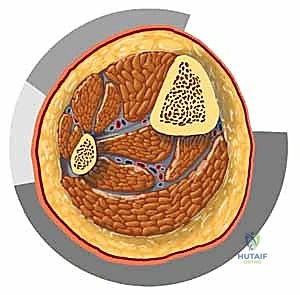

لفهم متلازمة الحيز، يجب أن نفهم تشريح الساق (المنطقة بين الركبة والكاحل). الساق مقسمة إلى أربع حجرات (Compartments) رئيسية، مفصولة عن بعضها البعض بواسطة حواجز ليفية قوية وعظام غير قابلة للتمدد. هذه الحجرات هي:

- الحيز الأمامي (Anterior Compartment): يحتوي على العضلات المسؤولة عن رفع القدم للأعلى (Dorsiflexion)، العصب الشظوي العميق، والشريان الظنبوبي الأمامي. هذا الحيز هو الأكثر عرضة للإصابة بمتلازمة الحيز.

- الحيز الجانبي (Lateral Compartment): يحتوي على العضلات التي تقلب القدم للخارج، والعصب الشظوي السطحي.

- الحيز الخلفي السطحي (Superficial Posterior Compartment): يحتوي على عضلات الساق الخلفية الكبيرة (السمانة) المسؤولة عن دفع القدم للأسفل، ويمر به العصب الربلي.

- الحيز الخلفي العميق (Deep Posterior Compartment): يقع بعمق تحت عضلات السمانة، ويحتوي على العضلات التي تثني أصابع القدم، بالإضافة إلى الشريان الظنبوبي الخلفي والعصب الظنبوبي. هذا الحيز خطير للغاية لصعوبة تشخيص الضغط فيه مبكرًا.

اللفافة المحيطة بهذه الحجرات قوية جدًا ولا تتمدد. لذلك، أي زيادة في حجم السوائل أو الدم داخل هذه الحجرات سيؤدي حتمًا إلى زيادة الضغط الداخلي.